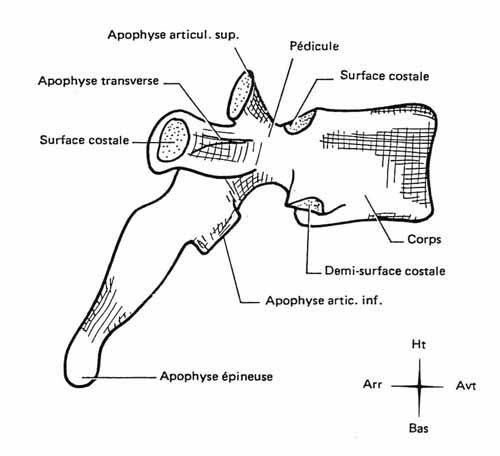

Tu peux analyser les lames sur le cliché de profil pour le rachis cervical, dorsal et lombaire ainsi que sur l’incidence de ¾ de lombaire où tu déroules les chiens de la chapelle

Les pédicules tu les analyses en coupe optique sur les incidences de face et sur le profil

Rachis cervical:  Rachis dorsal: Rachis dorsal:  Rachis lombaire: Rachis lombaire:   1. Processus articulaire supérieur 2. Pédicule droit 3. Processus transverse droit 4. Isthme 5. Processus articulaire inférieur 6. Lame opposée 7. Processus transverse opposé 8. Epineuse 9. Interligne articulaire postérieure 10. Processus articulaire inférieur opposé 11. Processus articulaire supérieur opposé Pour ce qui est de la radioanatomie; nous te laissons le soin d'apprendre tout cela grâce aux livres à ta disposition et à tes stages surtout!  Nous avions commencé une liste de livres de radiologie; à toi de t'en servir et bonnes recherches! Si tu souhaites trouver d'autres correspondances, si quelques détails t'interpellent n'hésite pas à poser des questions précises! Bon courage la marmotte!